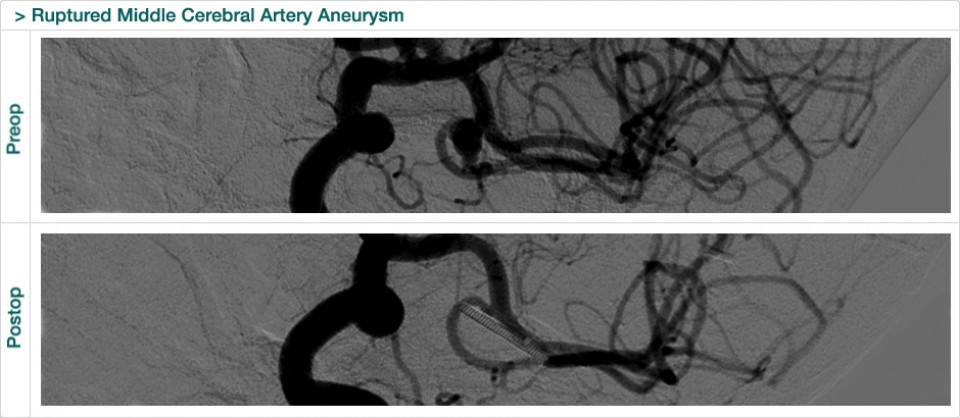

Dr. Attia is an attending neurosurgeon and the director of skull base surgery service in the department of neurosurgery at Sheba Medical Center in Tel HaShomer. His specialty focuses on skull base and cerebrovascular neurosurgery.